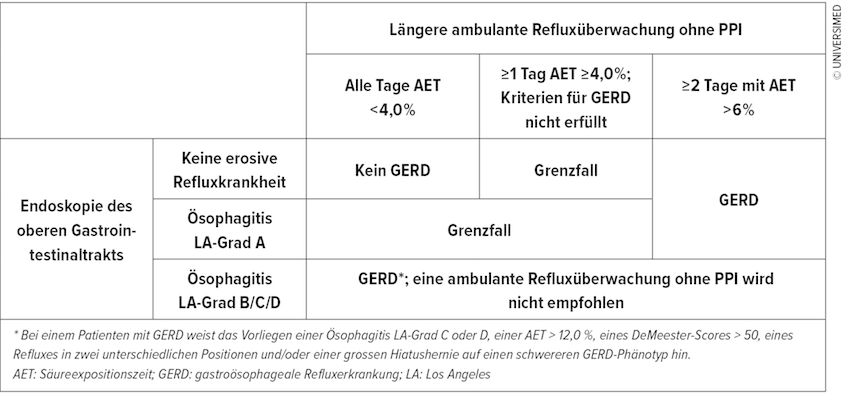

96h-Langzeit-pH-Metrie mittels «drahtloser» BRAVO®-Kapsel

Als alternative Methode zur 24h-Impedanz-pH-Metrie mittels transnasal eingelegtem Katheter hat sich in den letzten Jahren die «drahtlose» 96H-pH-Metrie mit der BRAVO®-Kapsel durchgesetzt. Die Untersuchung ist theoretisch bereits mit der Indexgastroskopie kombinierbar und erlaubt durch das verlängerte Aufzeichnungsintervall die Erkennung einer pathologischen GERD auch bei nur intermittierend auftretendem Reflux. Da die Patienten nicht durch einen transnasalen Katheter beeinträchtigt sind und lediglich das zur Symptomerfassung und pH-Dokumentation erforderliche Aufzeichnungsgerät mitführen müssen gelingt eine repräsentative Messung während des individuellen Tagesablaufs. Die Kapsel wird über ein Applikatorssystem an einer mittels Unterdruck generierten Mukosafalte 6cm oberhalb des ösophagogastralen Übergang (enstprechend 5cm oberhalb des unteren Ösophagussphinkters) mit einer Art Sicherheitsnadel in der Ösophagusmukosa fixiert und fällt nach wenigen Tagen spontan ab. Sie kann ein gewisses Fremdkörpergefühl auslösen, das vor allem für Patienten mit Reflux-Hypersensitivität unangenehm sein kann. Das System kann im Gegensatz zur Impedanz-pH-Metrie allerdings lediglich saure Refluxepisoden detektieren, sodass eine Untersuchung unter PPI nicht sinnvoll ist. Der Einsatz ist bei implantierten Defibrillatoren, Ösophagusvarizen, Divertikeln oder einer Nickel-Kobaltallergie kontraindiziert. Als pathologischer gastroösophagealer Reflux wird bei der BRAVO®-Kapsel-pH-Metrie eine Säureexpositionszeit des distalen Ösophagus von mehr als 6% an mindestens 2 von 4 Tagen gewertet. Ausserdem wird die Symptomkorrelation beurteilt. Die Untersuchung kann helfen, grenzwertige Fälle einer Refluxösophagitis (Endoskopie LA-Grad A) doch einer gastroösopheagealen Refluxerkrankung zuzuordnen (Abb. 2). Studien haben gezeigt, dass eine höhere Anzahl von Tagen mit normaler Säureexposition mit einer 5-fach höheren Wahrscheinlichkeit einhergeht, eine begonnene PPI-Therapie wieder absetzen zu können.

Abb. 2: Indikation zur 48/95h-Langzeit-ph-Metrie mittels drahtloser BRAVO®-Kapsel (nach Yadlapati et al., 2022)12